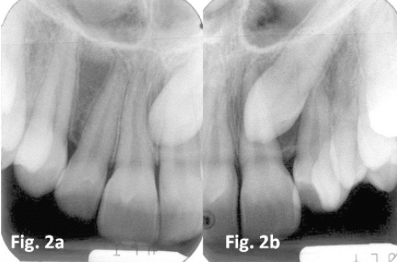

The upper canines usually erupt around [blank_start]11[blank_end] or [blank_start]12[blank_end] years of age. [blank_start]Congenitally[blank_end] absent canines is rare 0.3%. [blank_start]Impaction[blank_end] of canines is more common, and is usually bilateral. You should be able to [blank_start]palpate[blank_end] maxillary canines around 9 years of age in the buccal [blank_start]sulcus[blank_end]. Causes of impacted maxillary canines may be due to the: - [blank_start]Long[blank_end] path of eruption - [blank_start]Short[blank_end] rooted or [blank_start]absent[blank_end] upper lateral incisors ([blank_start]peg[blank_end] laterals) - Crowding - [blank_start]Retention[blank_end] of primary canine (an indicator rather than a cause!) - [blank_start]Genetic[blank_end] factors. It may run in the [blank_start]family[blank_end]. - It should also be noted that impacted canines is associated with other dental anomolies You should first assess the child [blank_start]clinically[blank_end] to see if you can tell where the tooth is displaced. If you suspect displacement you may wish to take some [blank_start]radiographs[blank_end]. The radiographs most commonly used for assessing ectopic canines are [blank_start]panoramic[blank_end] radiographs, upper [blank_start]occlusal[blank_end] radiographs, lateral [blank_start]cephalometric[blank_end] (for more accurate localisation), [blank_start]cone beam[blank_end] computerised tomography, and periodicals (useful for prognosis of retained deciduous canines). Management depends on wether the teeth are [blank_start]buccally[blank_end] or [blank_start]palatally[blank_end] displaced. Buccal displacements are usually due to [blank_start]crowding[blank_end], so relief of [blank_start]crowding[blank_end] is usually the option Palatal displacements may require surgical [blank_start]exposure[blank_end] with orthodontic [blank_start]alignment[blank_end], or surgical [blank_start]removal[blank_end] of the impacted canine. Occasionally unerupted canines can cause [blank_start]resorption[blank_end] of adjacent lateral incisor roots and possibly the centrals. In this case intervention should be done swiftly.

• buccally

• palatally

• resorption